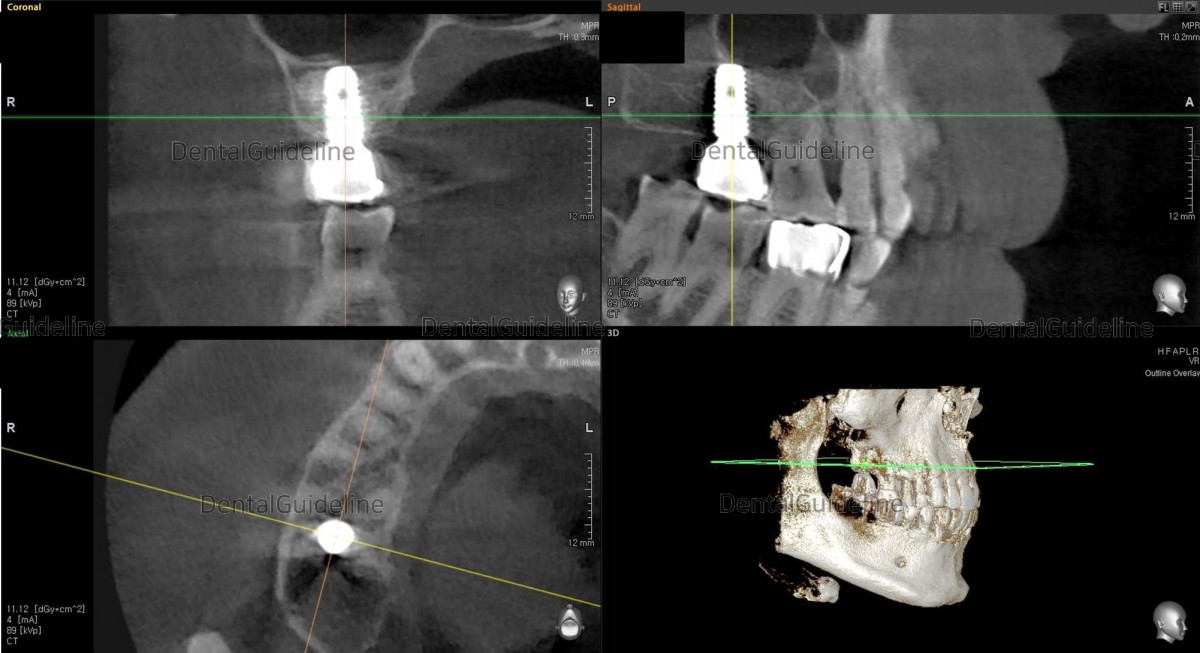

The implant was placed with the size of 5*10 Hiossen(=Osstem) TS. And HA was connected on-site at the same time.

CBCT